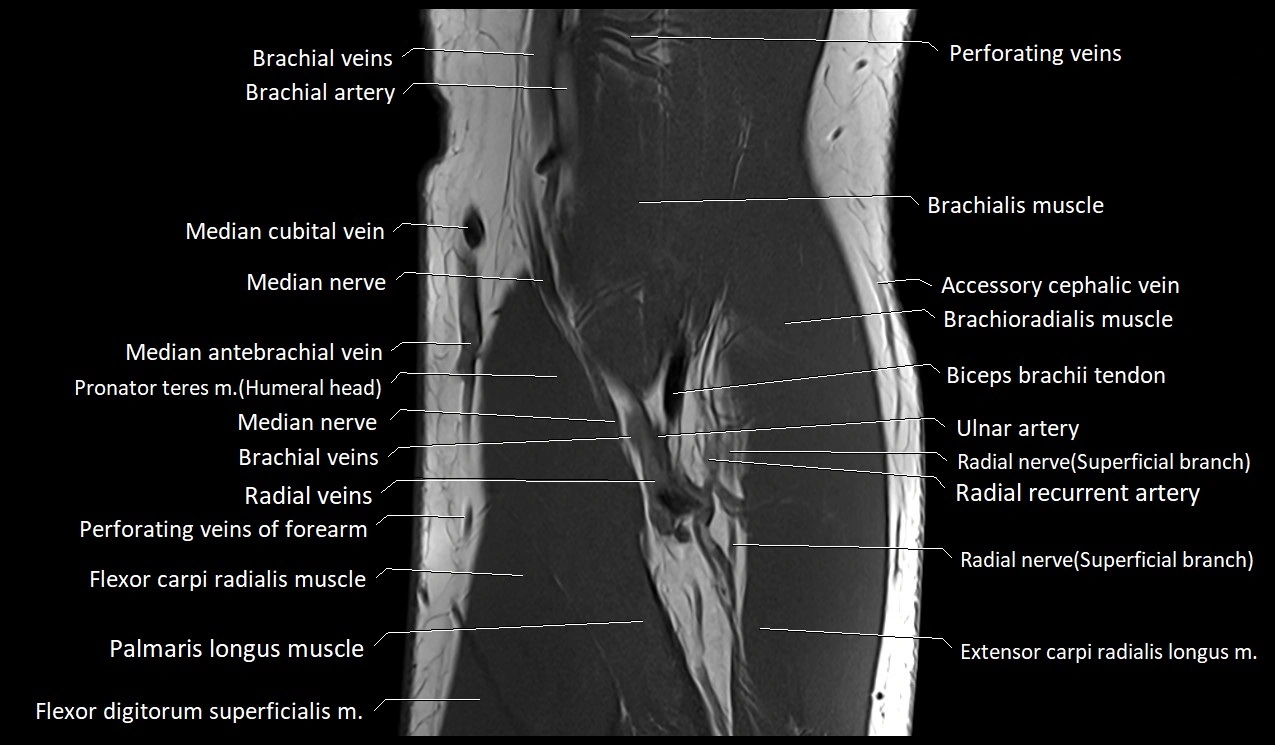

MRI image

image